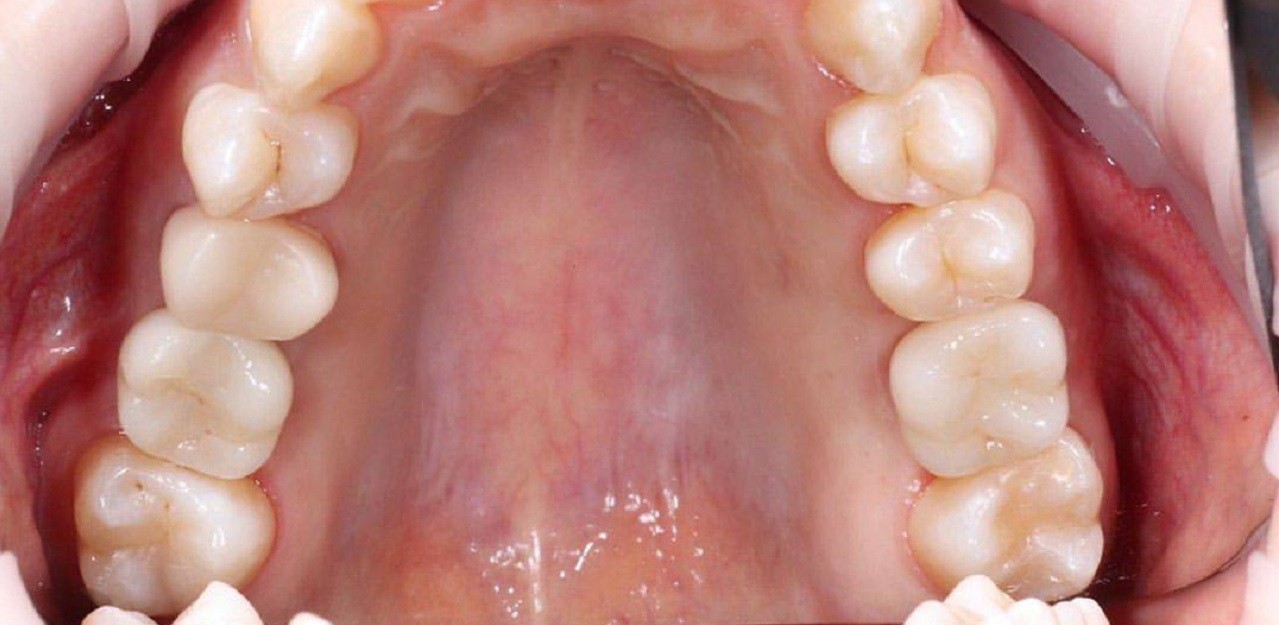

Вертикальная аугментация атрофированного альвеолярного отростка в области дистального участка нижней челюсти